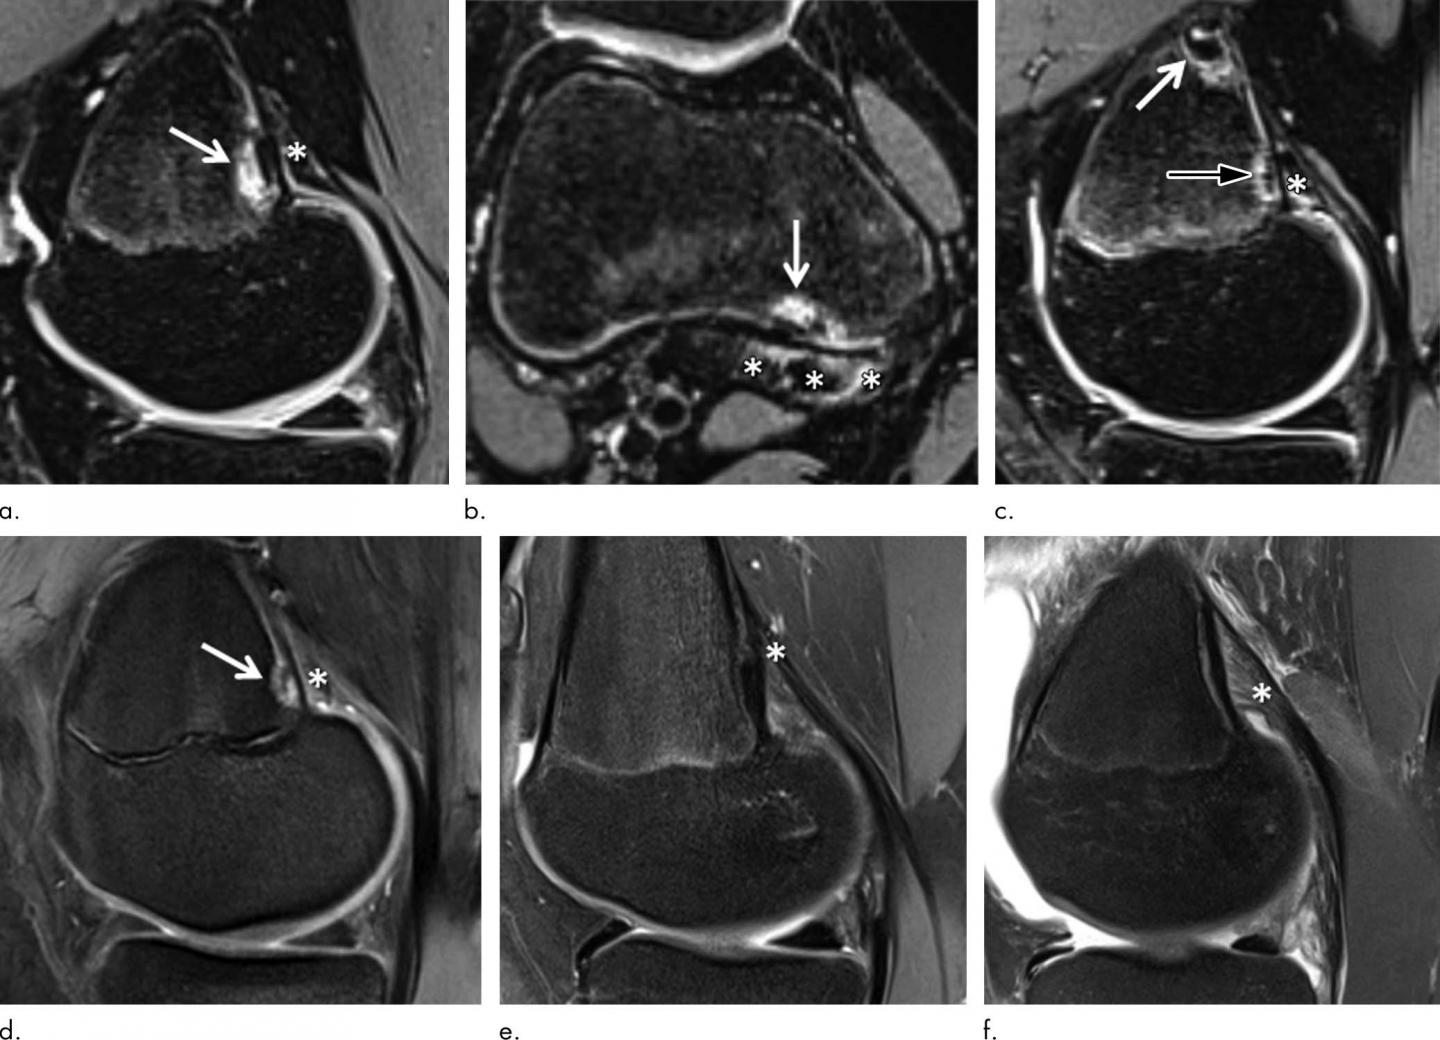

Routine knee MRI of adolescents often reveals tumor-like irregularities in the bone of the distal femur, the part of the thigh bone right above the knee. These irregularities affect the cortical bone, the dense outer surface of the bone. For that reason, they are referred to as distal femoral cortical irregularities (DFCI). DFCI often lead to diagnostic uncertainty because they can be confused with more serious conditions like cancer or infection.

The researchers compared the knee MRIs of 105 youth competitive alpine skiers with those of 105 controls of the same age group collected from 2014 to 2019. They looked for the presence of DFCI at two tendon-bone attachment areas: the ones between the gastrocnemius--the major muscle of the calf--and the femur, and the ones between the adductor magnus muscle of the inner thigh and the femur.

DFCIs were observed at the attachment sites of tendons, predominantly at the inside head of the gastrocnemius muscle for both skiers and controls.

"DFCI are benign lesions, and occurrence around the knee joint is associated with repetitive mechanical stress to the attachment sites of tendons into bone," Dr. Stern said. "DFCI should not be mistaken for malignancy and are not associated with intraarticular damage."

The most common theory behind the DFCI occurrence is that of a "tug lesion" as a result of repetitive mechanical stress where the tendons attach to the bone.